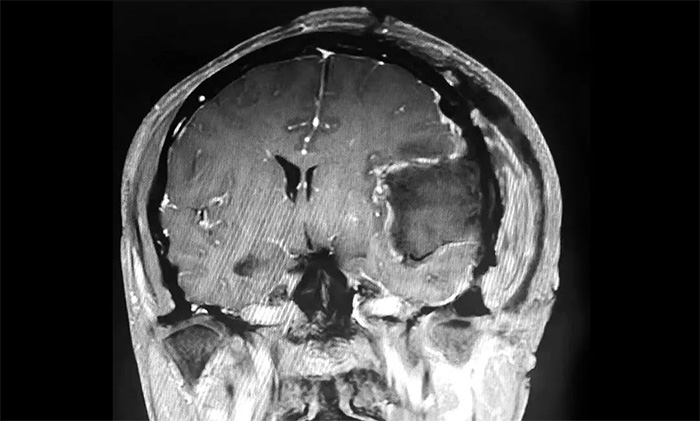

2023年12月7日,在進(jìn)一步完善術(shù)中應(yīng)急預(yù)案,做好充分準(zhǔn)備后,沈建康主任與于耀宇主任聯(lián)手,開(kāi)展了高難度的巨大腦膜瘤切除手術(shù)。

▲ 腫瘤順利切除

手術(shù)取左側(cè)額顳頂部入路,在顯微鏡下,沈建康主任與于耀宇主任通力協(xié)作,仔細(xì)分離腫物周邊密集的神經(jīng)血管,逐步分塊切除腫物及附著的硬膜。切除腫瘤后,術(shù)區(qū)瘤腔未見(jiàn)活動(dòng)性出血。歷時(shí)5小時(shí),手術(shù)順利完成,留取病理標(biāo)本送檢。

▲ 病理分析確定為纖維型腦膜瘤(WHO 1級(jí))

術(shù)后,患者生命體征平穩(wěn),安返監(jiān)護(hù)病房。經(jīng)對(duì)留取的腫物樣本進(jìn)行病理分析,確定為纖維型腦膜瘤(WHO 1級(jí)),為良性腫瘤。